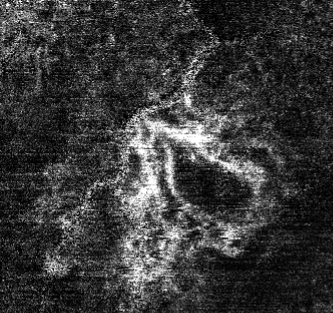

The Data Cleaning phase (Fig. 5) consists of two steps: image cropping and Gaussian filtering for smoothing. In reality, the blood vessel is typically represented as a single piece. However, the process of capturing the OCTA image tends to distort some images, making a vessel appear fragmented, even though it is actually a single continuous thread. Without this phase, relevant information could be lost, or simple artifacts might be misinterpreted as blood vessels.

In Fig. 6, one can observe that the input image has a granular structure, causing the object pixels to appear disconnected. A significant number of background pixels interfere with the visualization of the blood vessels.